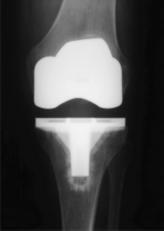

Bei einem künstlichen Kniegelenk werden die natürlichen Oberflächen

des Kniegelenkes teilweise oder vollständig ersetzt. Die Prothese

besteht aus einer Oberschenkelkappe und einer Schienbeinplatte aus

hochpoliertem Metall, und einem aus Polyethylen gefertigten

Gleitflächenersatz. In unserer Klinik werden sowohl Oberschenkelkappe

als auch die Schienbeinplatte mit Knochenzement verankert, da Studien

die Überlegenheit dieser Verankerungsmethode gegenüber der zementfreien

Verankerungen am Knie zeigten.

Bei fortgeschrittenem Gelenkverschleiß sollte eine totale

Knieendoprothese implantiert werden. Wenn die natürliche Bandführung

eine ausreichende Stabilität des Gelenkes gewährleistet, was bei den

meisten Patienten der Fall ist, so wird ein ungekoppelter

Oberflächenersatz verwendet.

Besteht jedoch auch eine fortgeschrittene Schädigung des

Kapsel-Band-Apparates,

so ist die Implantation einer sich selbst

stabilisierenden achsgeführten Endoprothese indiziert. Bei einer

nachgewiesenen Nickelallergie verwenden wir ein nickelfreies Modell aus

oxidiertem Zirconium.